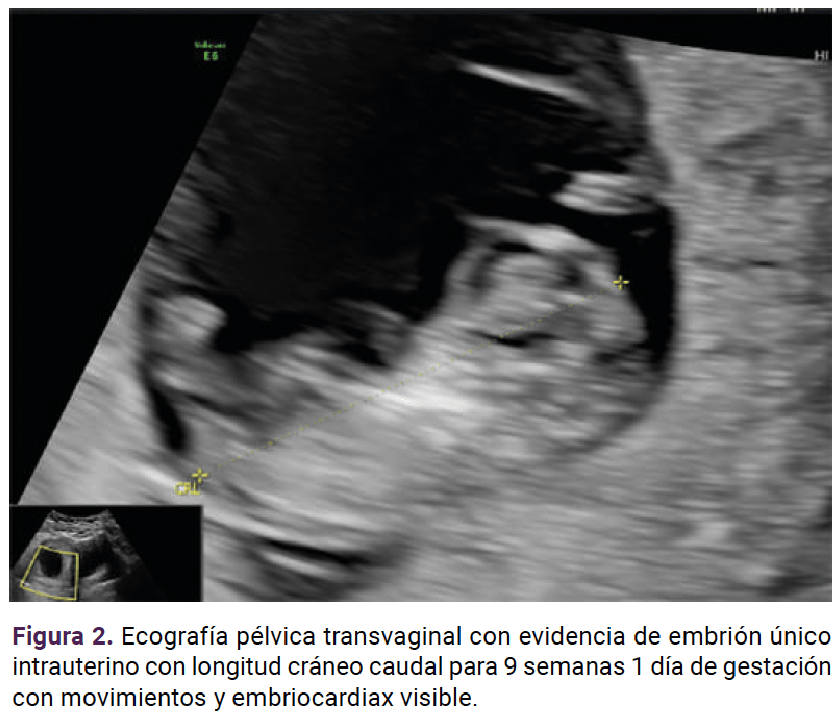

Luego de una hora de la transfusión de la última unidad de glóbulos rojos, la paciente se encontró en regulares condiciones generales, con disnea y signos vitales de: presión arterial: 101-64 mmHg, media de 80 mmHg, frecuencia cardiaca de 101 lpm, frecuencia respiratoria: 19 rpm, temperatura: 36.3 °C, saturación arterial de oxígeno: 93% con requerimiento de oxígeno de alto flujo con máscara de no reinhalación, estertores bibasales de predominio izquierdo, ecografía de pleura con signos de sobrecarga dados por derrame pleural, gases arteriales en equilibrio ácido base, normoxemia, con severo trastorno de la oxigenación con PAFI: 78. La placa de tórax se observó con opacidades bibasales, y BNP elevado. Se consideró una reacción adversa transfusional tipo TACO. Se inició la administración de un diurético, corticoide y ciclos de ventilación mecánica no invasiva. A las 8 horas, la paciente mostró una adecuada respuesta al tratamiento. Los gases arteriales de control se reportaron en equilibrio ácido base y moderado trastorno de la oxigenación con PAFI de 160. Se logró el control del trastorno de oxigenación 24 horas después del inicio de los ciclos de ventilación mecánica no invasiva. Tres días después del inicio del soporte vasopresor fue posible retirarlo, por evidencia notable de la mejoría clínica. El hemograma de control reportó concentraciones de leucocitosis en límites de normalidad, aunque con persistencia de la anemia sin criterios de transfusión: leucocitosis de 7520, neutrófilos del 57%, hematocrito 27.12%, hemoglobina: 9.47 g/dL y 198,300 plaquetas. En la ecografía obstétrica de control se verificó la vitalidad fetal, con evidencia de embarazo intrauterino de nueve semanas, por longitud cráneo-caudal. Figura 2

<strong>Figura 2</strong>

Figura 2